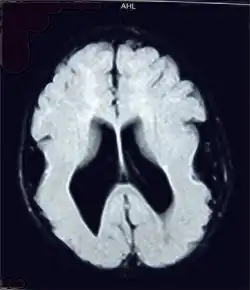

![]() Cerebro con lisencefalia. | ||

La lisencefalia, término que literalmente significa «cerebro liso»,[1] es un trastorno poco común de la formación del cerebro caracterizado por microcefalia y agiria (lisencefalia completa), que es una ausencia de las circunvoluciones o gyrus (pliegues) normales del cerebro. Es causada por una migración neuronal defectuosa, el proceso en el cual las células nerviosas se desplazan desde el lugar de origen a su localización permanente.[2] Este término no caracteriza una enfermedad sino un grupo de enfermedades (Trastornos del espectro de la lisencefalia).[3]

La superficie de un cerebro normal está formada por una serie compleja de pliegues y canales. Los pliegues se denominan giros (gyri) o circunvoluciones y los canales se denominan surcos (sulci).[5] En niños que padecen de lisencefalia, las circunvoluciones normales están ausentes o se han formado solamente en parte, haciendo que la superficie del cerebro sea lisa.[1]